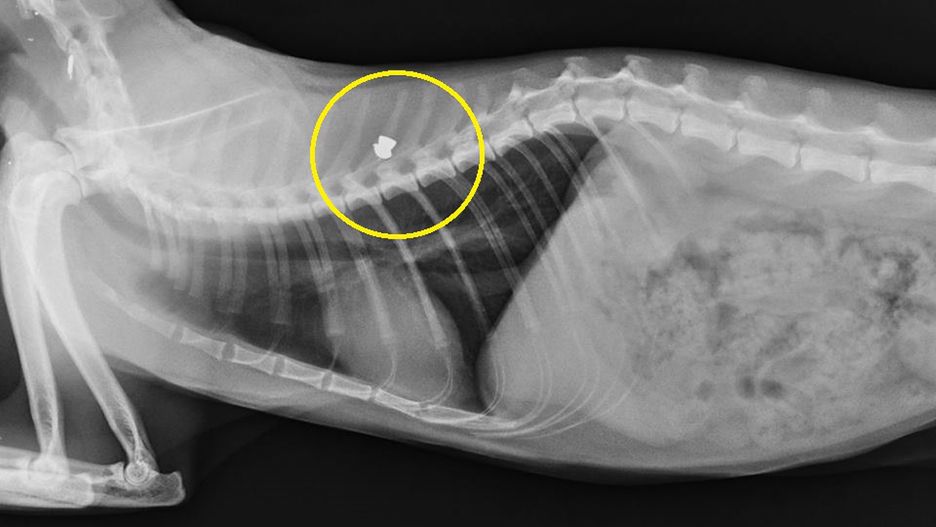

Właściciel jednej z lecznic weterynaryjnych w gminie Michałowice zamieścił na Facebooku zdjęcia kotów postrzelonych z wiatrówki. W ciałach ranionych zwierząt znaleziono ołowiane pociski. Do podobnych zdarzeń dochodziło już wcześniej.

W ciągu ostatnich dwóch dni do lecznicy trafiły dwa inne koty. Oba postrzelone. Policjanci z komendy w Michałowicach twierdzą, że sygnały o postrzelonych kotach z Komorowa i okolic docierały do nich już wcześniej, jednak do tej pory nikt nie złożył zawiadomienia w tej sprawie.